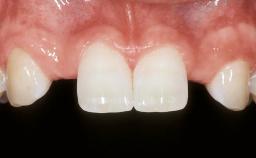

In September of 1995, a 64-year-old female patient presented to our clinic with a distally shortened arch in the left maxilla and the desire for a fixed rehabilitation. The patient’s medical history did not reveal any major issues, and she did not take any significant medication. She was a non-smoker and did not report any allergies.The patient wished to restore her chewing function on the left side, which was severely compromised due to the missing teeth 25, 26, and 27. The antagonistic lower teeth were present and in acceptable condition.